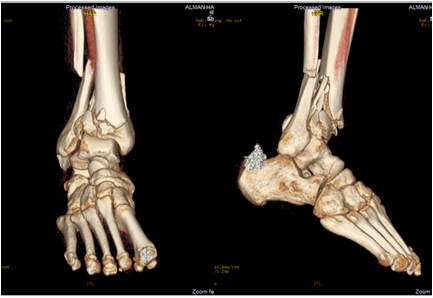

Ayak Bileği Rahatsızlıkları

AYAK BİLEĞİ BURKULMALA...